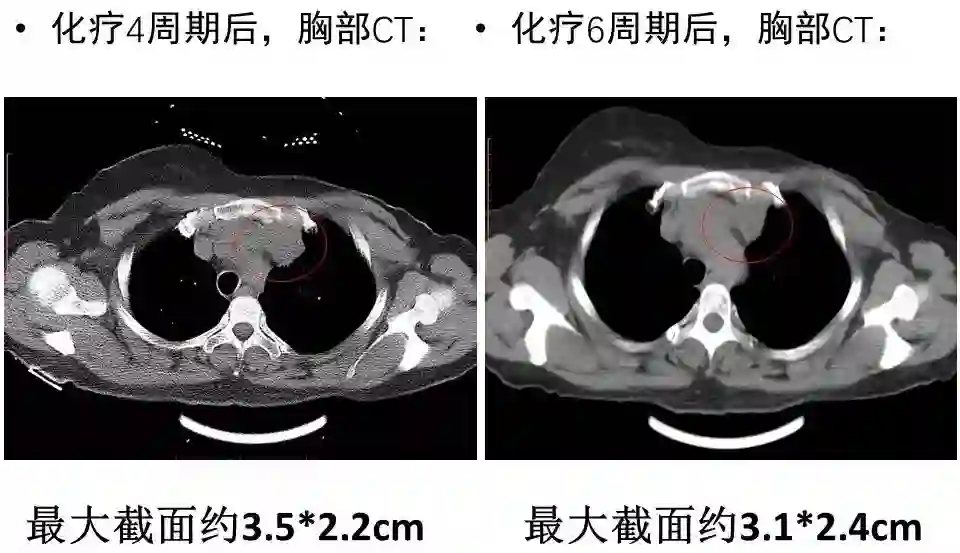

接受TC(卡铂)+曲妥珠单抗单周方案治疗。治疗2个周期后复查:淋巴结彩超示:左锁骨上淋巴结缩小,大的0.6×0.4cm;复查胸部CT示:左侧纵隔肿物缩小,最大截面约6.0×2.9cm。治疗4个周期后再次复查,淋巴结彩超示:左锁骨上淋巴结缩小,大的0.6×0.4cm;复查胸部CT示:左侧纵隔肿物缩小,最大截面约3.1×2.4cm。治疗6个周期后再次复查,淋巴结彩超示:左锁骨上淋巴结缩小,大的0.3×0.3cm;复查胸部CT示:纵膈肿物缩小明显,病灶局部包绕头臂静脉,与胸壁边界不清。评价治疗有效,继续行TC(卡铂)方案化疗+靶向治疗。治疗8周期后再次胸部CT示:纵隔肿瘤缩小明显,最大截面由最初的7.2×2.9cm缩小为2.7×2.9cm,评价为PR。8周期治疗后,患者出现腹泻,大便次数8-10次/天,水样便,影响日常生活,根据NCI分级属3级重度腹泻。10天左右缓解;II度骨髓抑制。患者拒绝继续化疗,曲妥珠单抗改为21天/周期。

图2. 治疗2周期后复查胸部CT平扫

图3. 治疗4周期后复查胸部CT平扫

图4. 治疗6周期后复查胸部CT平扫

图5. 治疗8周期后复查胸部CT平扫